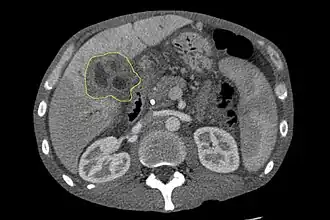

L'échographie du foie et des voies biliaires est souvent utilisée comme première méthode d'imagerie auprès des patients chez qui l'on suspecte un ictère (jaunisse) obstructif[51],[52]. Cette forme d'imagerie peut identifier l'obstruction et/ou une dilatation biliaire, ce qui, dans certains cas, peut s'avérer suffisant pour diagnostiquer un cholangiocarcinome[53]. On peut aussi utiliser l'écho-endoscopie qui permet l'ablation des polypes de petite taille avant leur transformation en carcinome[54],[55]. Le scanner tomodensitométrique peut aussi donner des informations diagnostiques du cholangiocarcinome[56],[57],[58]. La précision du diagnostic par tomodensitométrie est satisfaisante mais peut induire une sous-estimation de la dissémination de la tumeur dans les voies biliaires[59].